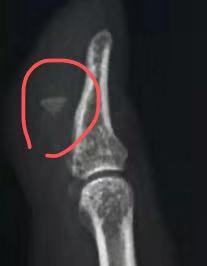

X线照片也证实了医生的猜想:大拇指指骨旁有明显的异物存在。

在随后的急诊手术中,我们从刘女士的大拇指中取出了一颗约3毫米大小的玻璃碴。